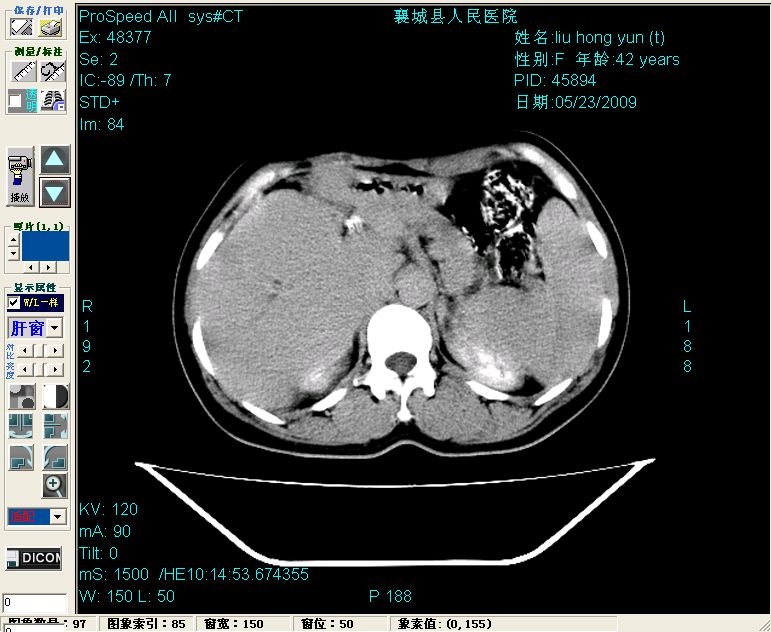

增强:

增强动脉期前述低密度区轻度早其强化,门脉期强化程度显著增高,延期扫描强化程度下降,但仍为相对高密度影

胰头部见结节状高密度影,其前方略可分辨扩强胆部管,平扫到增强始终有,但现在尚难与胃肠造影剂鉴别.

结合病史考虑,1现在引起黄疸体征的原因应该是胆总管胰段结石阻塞,建议局部胃肠造影剂排空后复查.